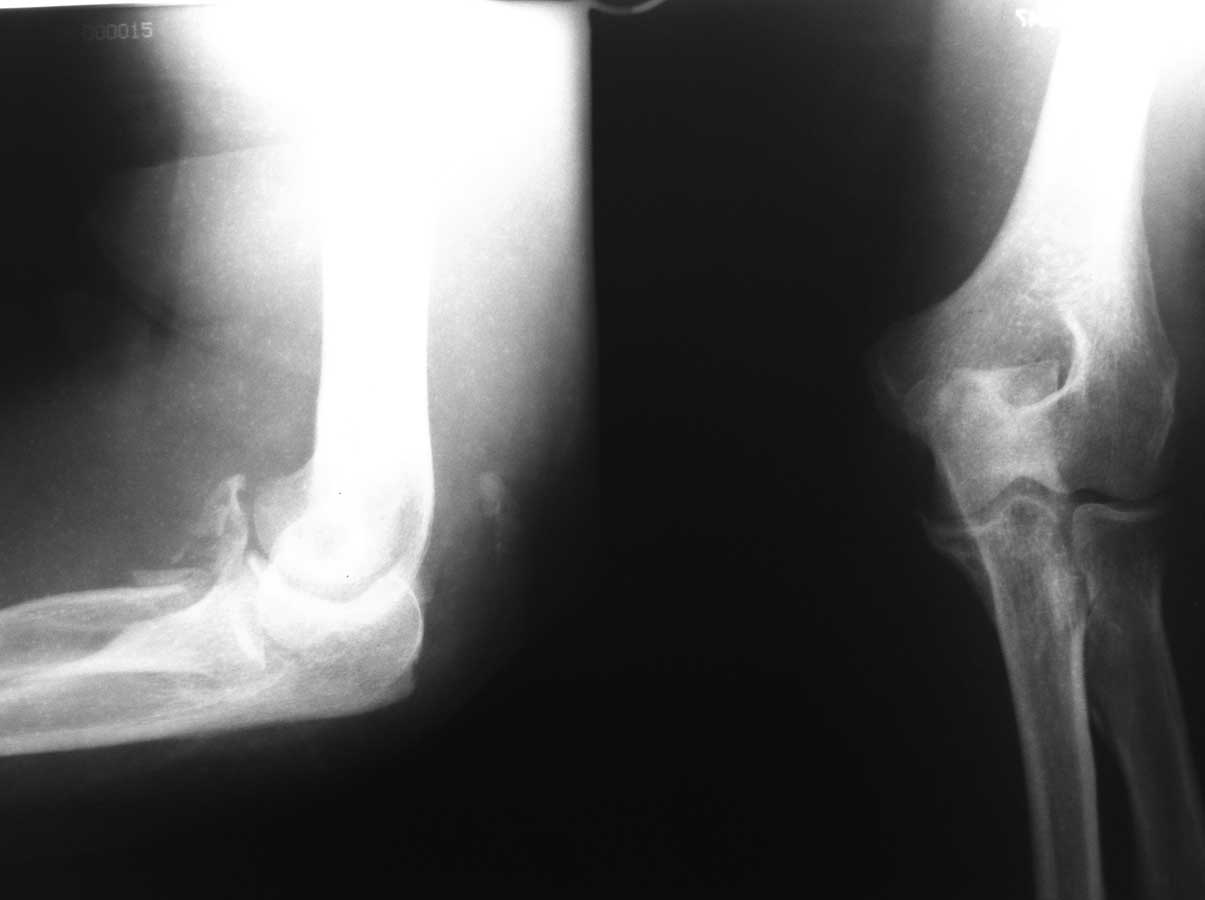

Пациентка 66 лет. Травма в результате падения на руку 12.04.2012. при обращении в п-ку

выполнены Р-гр.

21.05.2012 выполнены контрольные Р-гр и больная направлена на госпитализацию. Местно:

Отека нет, сосудистых и неврологических расстройств в конечности нет. движения в локтевом

суставе 10-15 гр умерено болезненные. Планируется - Открытое устранение дислокации в

суставе, резекция головки лучевой кости. Чем фиксировать сустав после операции (

гипс?АВФ?)